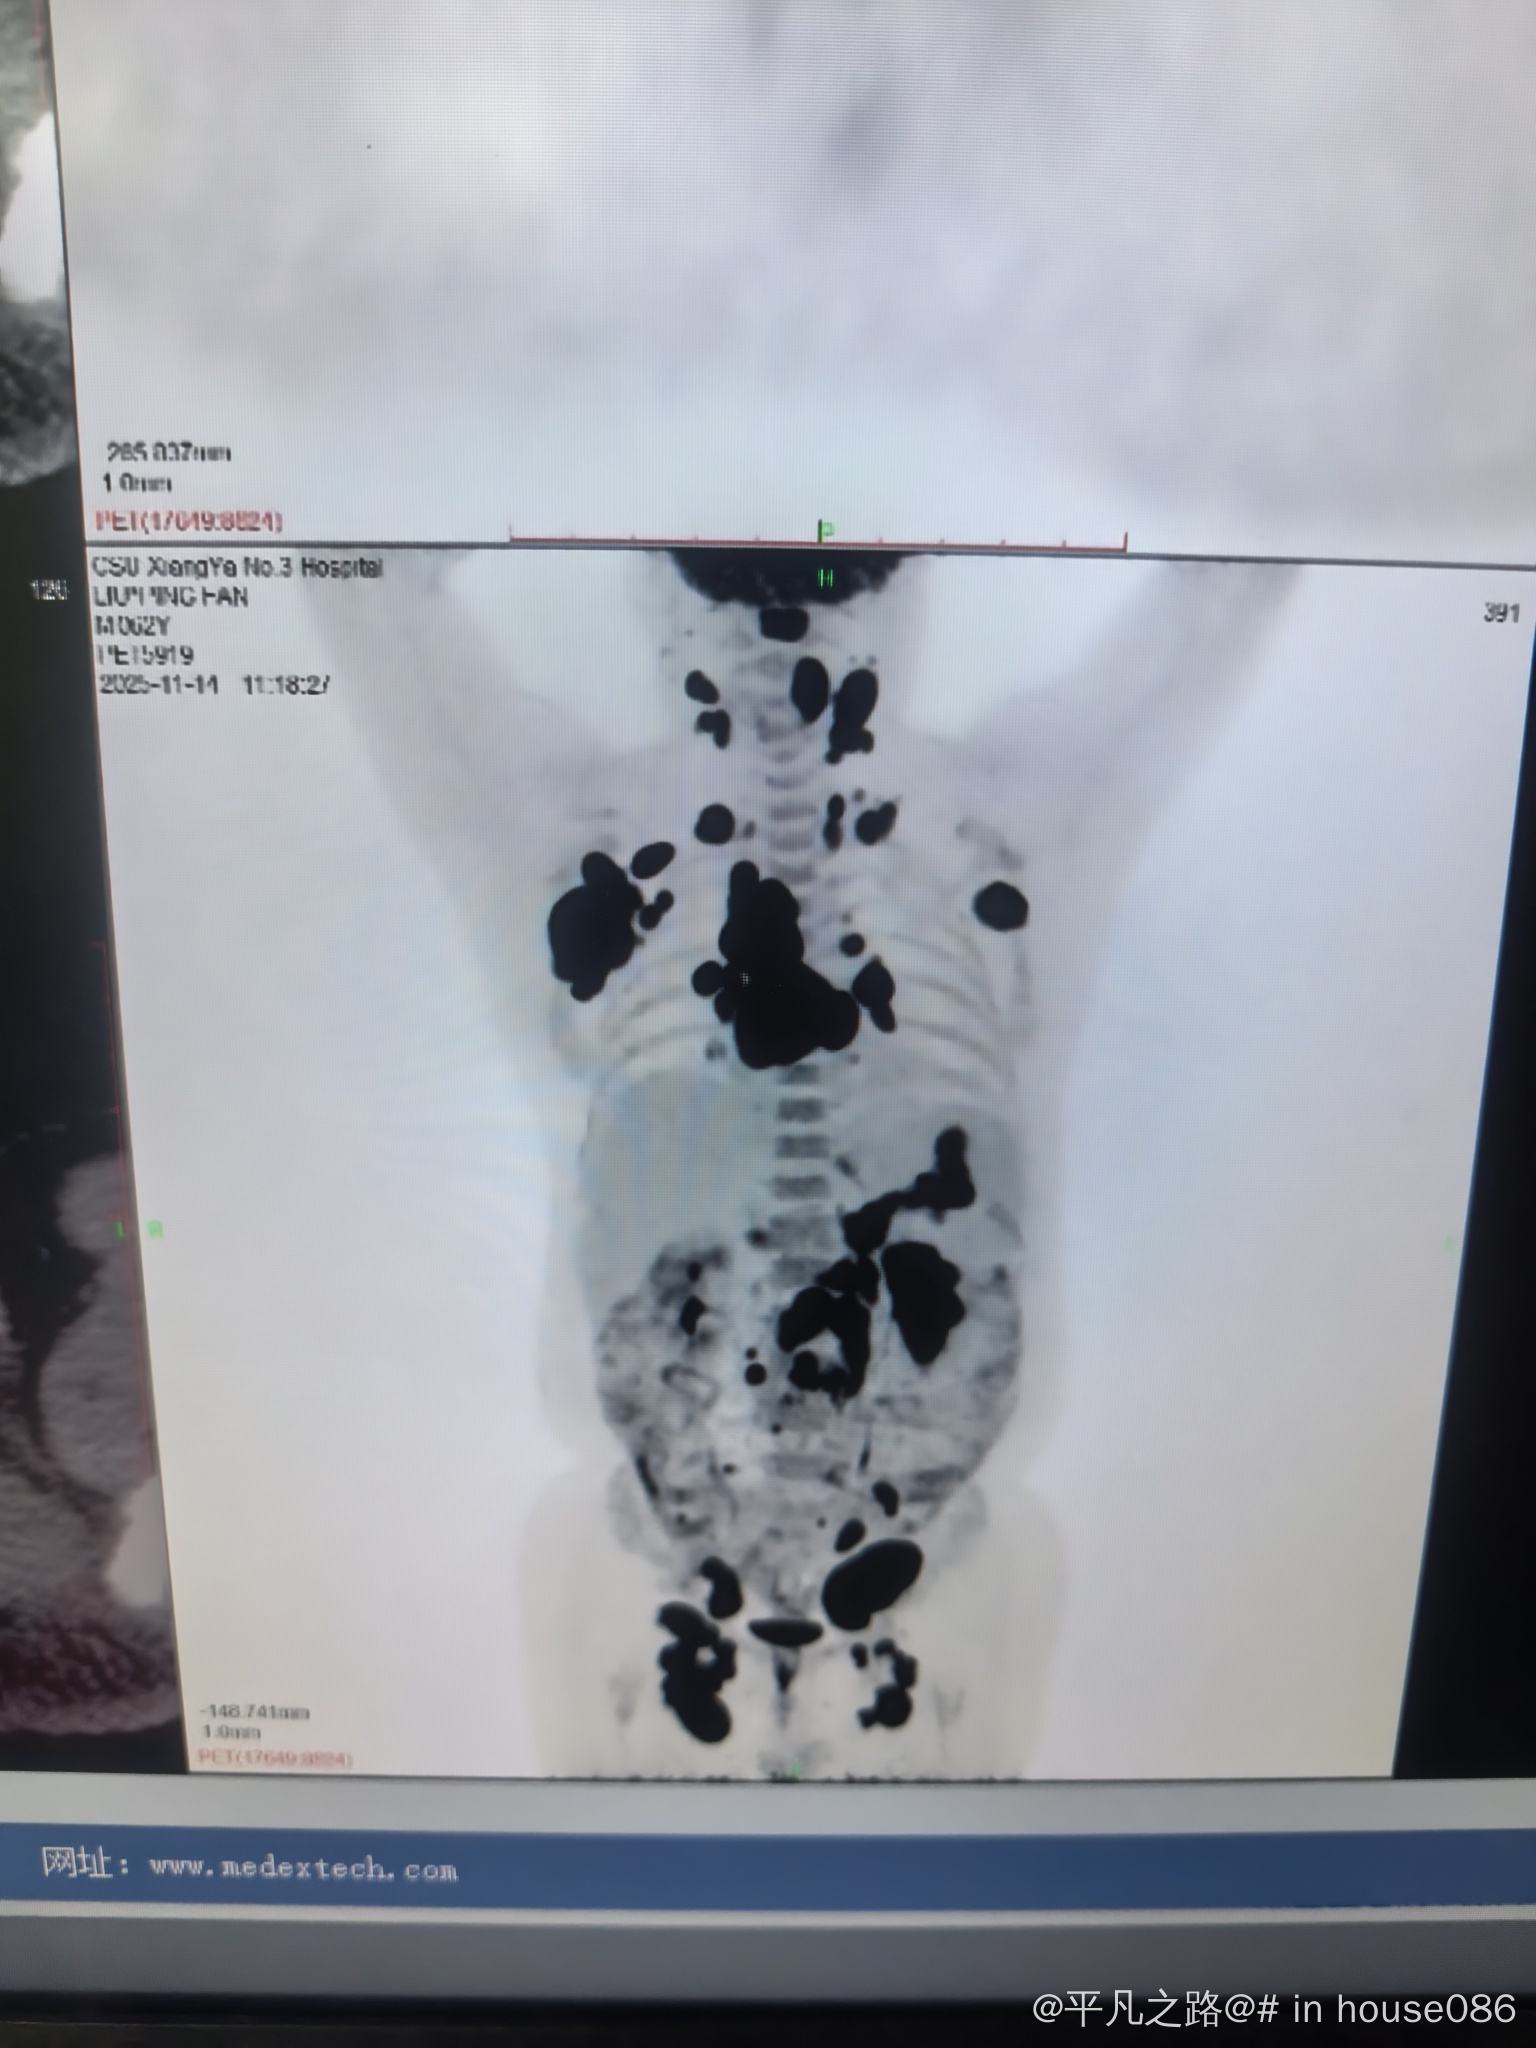

大家好,我想请问一下,我在湘雅三医院确诊的,我爸比较严重等不了了必须马上化疗,确定了 pola-R-CHP 方案。今天已经开始化疗,还有必要去湖南省肿瘤医院找周辉咨询吗?

弥漫大b细胞

湘雅三医院